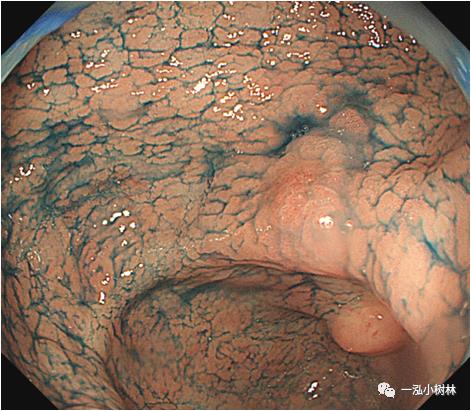

例1 胃窦病变

图1b 色素内镜:喷洒靛胭脂后可见病变边界清晰,病变处胃小区及胃小沟消失,病变处发红,靛胭脂不着色。